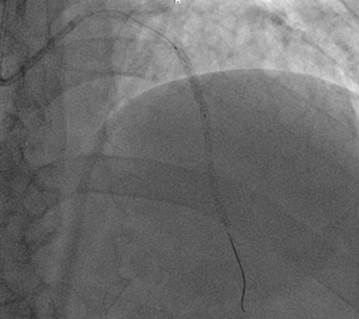

Se decidió realizar angioplastia coronaria percutánea a la DA colocándose 2 stent medicado 3 x 20 mm en tercio proximal y medio (Ilustración 5)

No hubo complicaciones durante el procedimiento.

Ilustración 5 Angioplastia con stent en descendente anterior.

Fuente: Hospital de Especialidades Guayaquil “Doctor Abel Gilbert Pontón”.